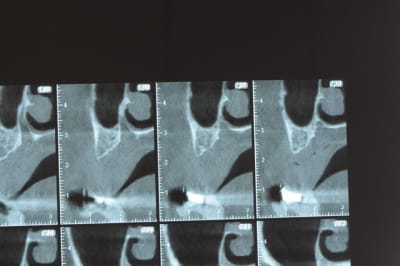

un cas pour PXAV.

j'ai besoin de 4 implants au maxillaire pour faire tenir son complet.

dans la zone postérieur, pas de problème, mais devant, c'est une autre histoire.

avant de faire la tomosynthèse je comprenais pas pourquoi j'avais aussi peu de contraste.

Une petite étude de ton cas D57

Les zones exploitables radiologiquement parlant:

Coupes implant